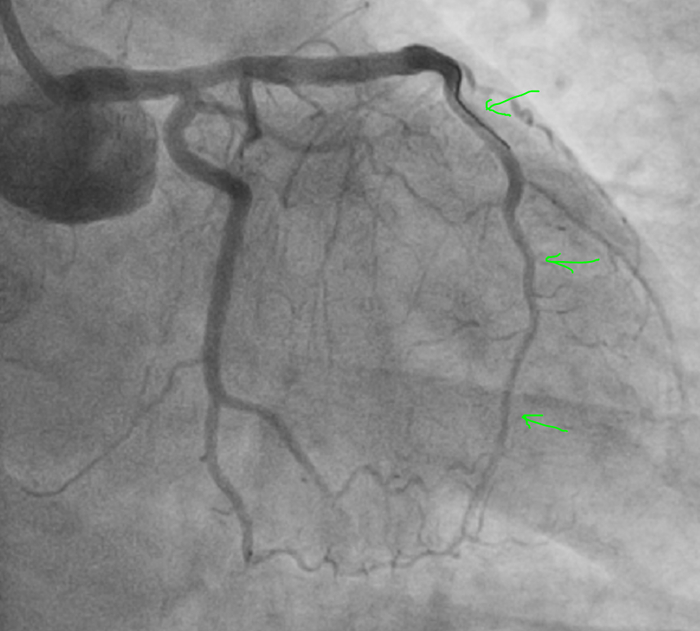

Результат:

Для контроля как стоит стент и дальнейших перспектив провели ОКТ (оптическую когерентную томографию) - завели что то вроде световода в коронарную артерию и просветили стенки лазером, в итоге получили такой результат:

Результат отличный.